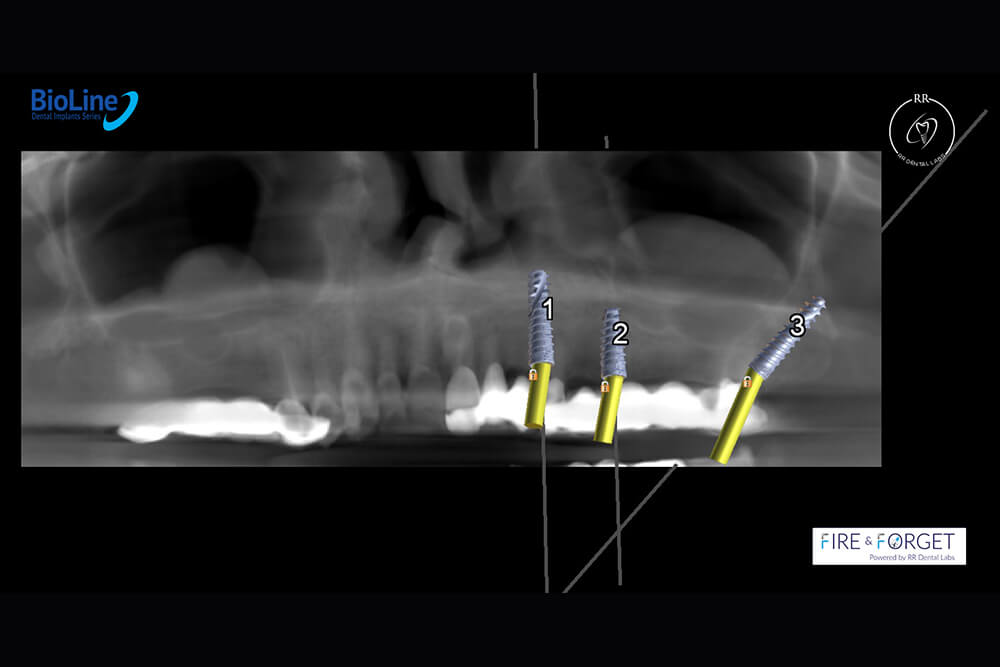

Case 47